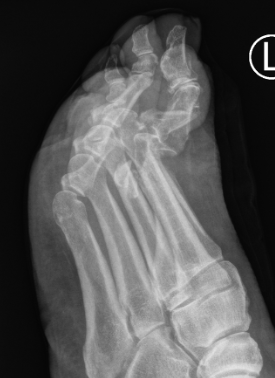

Great toe MTPJ dislocation

Pathology

Hyperdorsiflexion

Metatarsal head dislocates plantar

- tear of plantar plate / disruption bipartite sesamoid

- may buttonhole through capsule / plantar plate

Xray